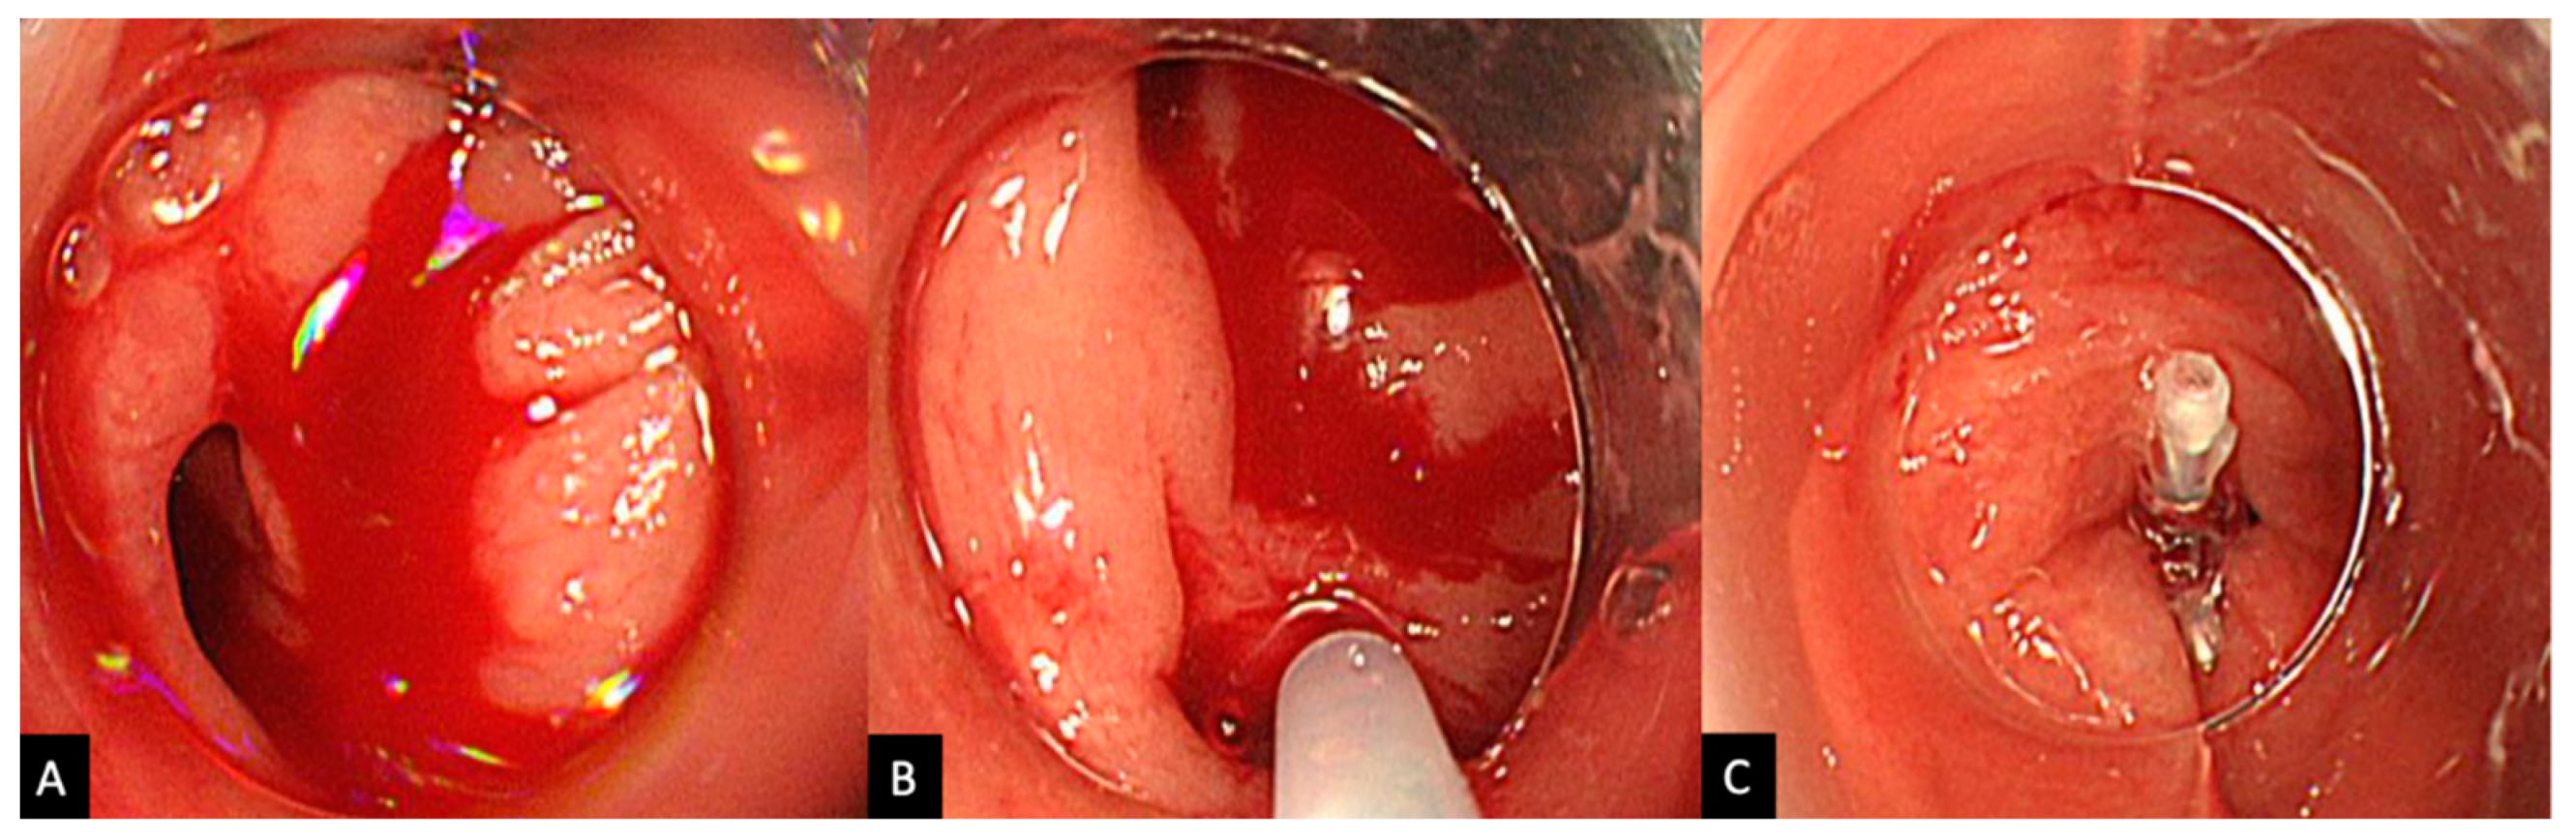

2.2. Procedure